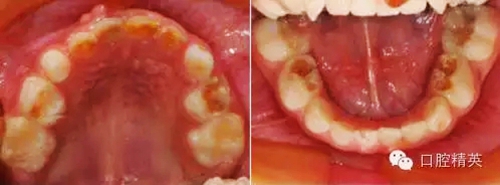

臨床檢查:頜面部及頸部未見(jiàn)明顯異常。口腔衛(wèi)生狀況尚可, 52,61,62,63,73唇舌面齲,54,64,74,84牙合面齲壞,腐質(zhì)中等,叩(-),松(-),牙齦未見(jiàn)明顯異常;75牙合面深齲壞,大量軟腐,叩(-),松(-),牙齦未見(jiàn)明顯異常,腐質(zhì)未去凈見(jiàn)露髓孔;51大面積齲壞,大量腐質(zhì),叩(+),松(Ⅰ),唇側(cè)牙齦可見(jiàn)5mm×6mm的包,軟;余牙未見(jiàn)異常。

診斷:S-ECC

①52,61,62,63,73,54,64,74,84去腐備洞,氫氧化鈣墊底,全酸蝕,DE-BOND加3M樹(shù)脂充填,調(diào)合,磨光。

②75,51局麻下開(kāi)髓、拔髓,根管預(yù)備,生理鹽水沖洗,Vitapex根充,鋅汀墊底,全酸蝕,DE-BOND加3M樹(shù)脂充填,調(diào)合,磨光。